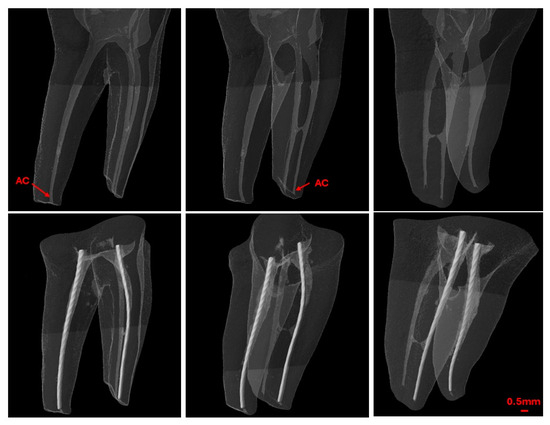

Background: Determining the correct apical limit for root canal treatment is essential for its success. This study evaluates the accuracy of three electronic apex locators (EALs) in locating the apical constriction (AC) in molar canals. Methods: Forty extracted human mandibular molars were scanned using micro-CT, and endodontic access cavities were created. Teeth were mounted in alginate, and three EALs—Root ZX-mini, Root ZX-II, and Sirona integrated apex locator—were used to measure the canal working length in dry canals and with EDTA gel. Micro-CT scans were performed with files in place, and the distance from the AC was calculated. Measurements within 0.1–0.5 mm were categorized as ‘close’. Those extending beyond towards the major foramen were categorized as ‘beyond’, otherwise they were classified as ‘far’. Data analysis was conducted with a level of significance set at 5%. Results: Most readings for all EALs were in the ‘close’ category, with significant differences between devices (p < 0.0001). Root ZX-mini and Root ZX-II had 74.4% and 72.5% ‘close’ readings, respectively, versus 51% for Sirona integrated. Accuracy did not differ significantly between dry and EDTA-treated canals (p = 0.306). All EALs demonstrated excellent operator reliability (ICC 0.996–1.00). Conclusions: All EALs accurately determined AC, unaffected by lubricants. However, Root ZX-mini and Root ZX-II outperformed Sirona integrated. All EALs showed consistent reliability. Full article